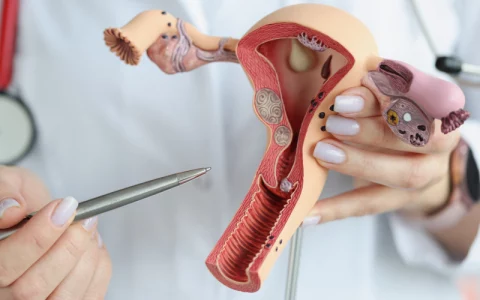

در طول دوران بارداری، توجه به رشد و تکامل جنین بسیار مهم است. از آزمایشهای ضروری مانند غربالگریها گرفته تا معاینات ماهانه، همه برای بررسی سلامت جنین انجام میشوند. همچنین، مطالعه درباره رشد و تربیت کودک و آمادگی برای یک تا ۱۲ ماهگی نوزاد، میتواند به والدین کمک کند تا برای این مرحله از زندگی آمادهتر باشند.